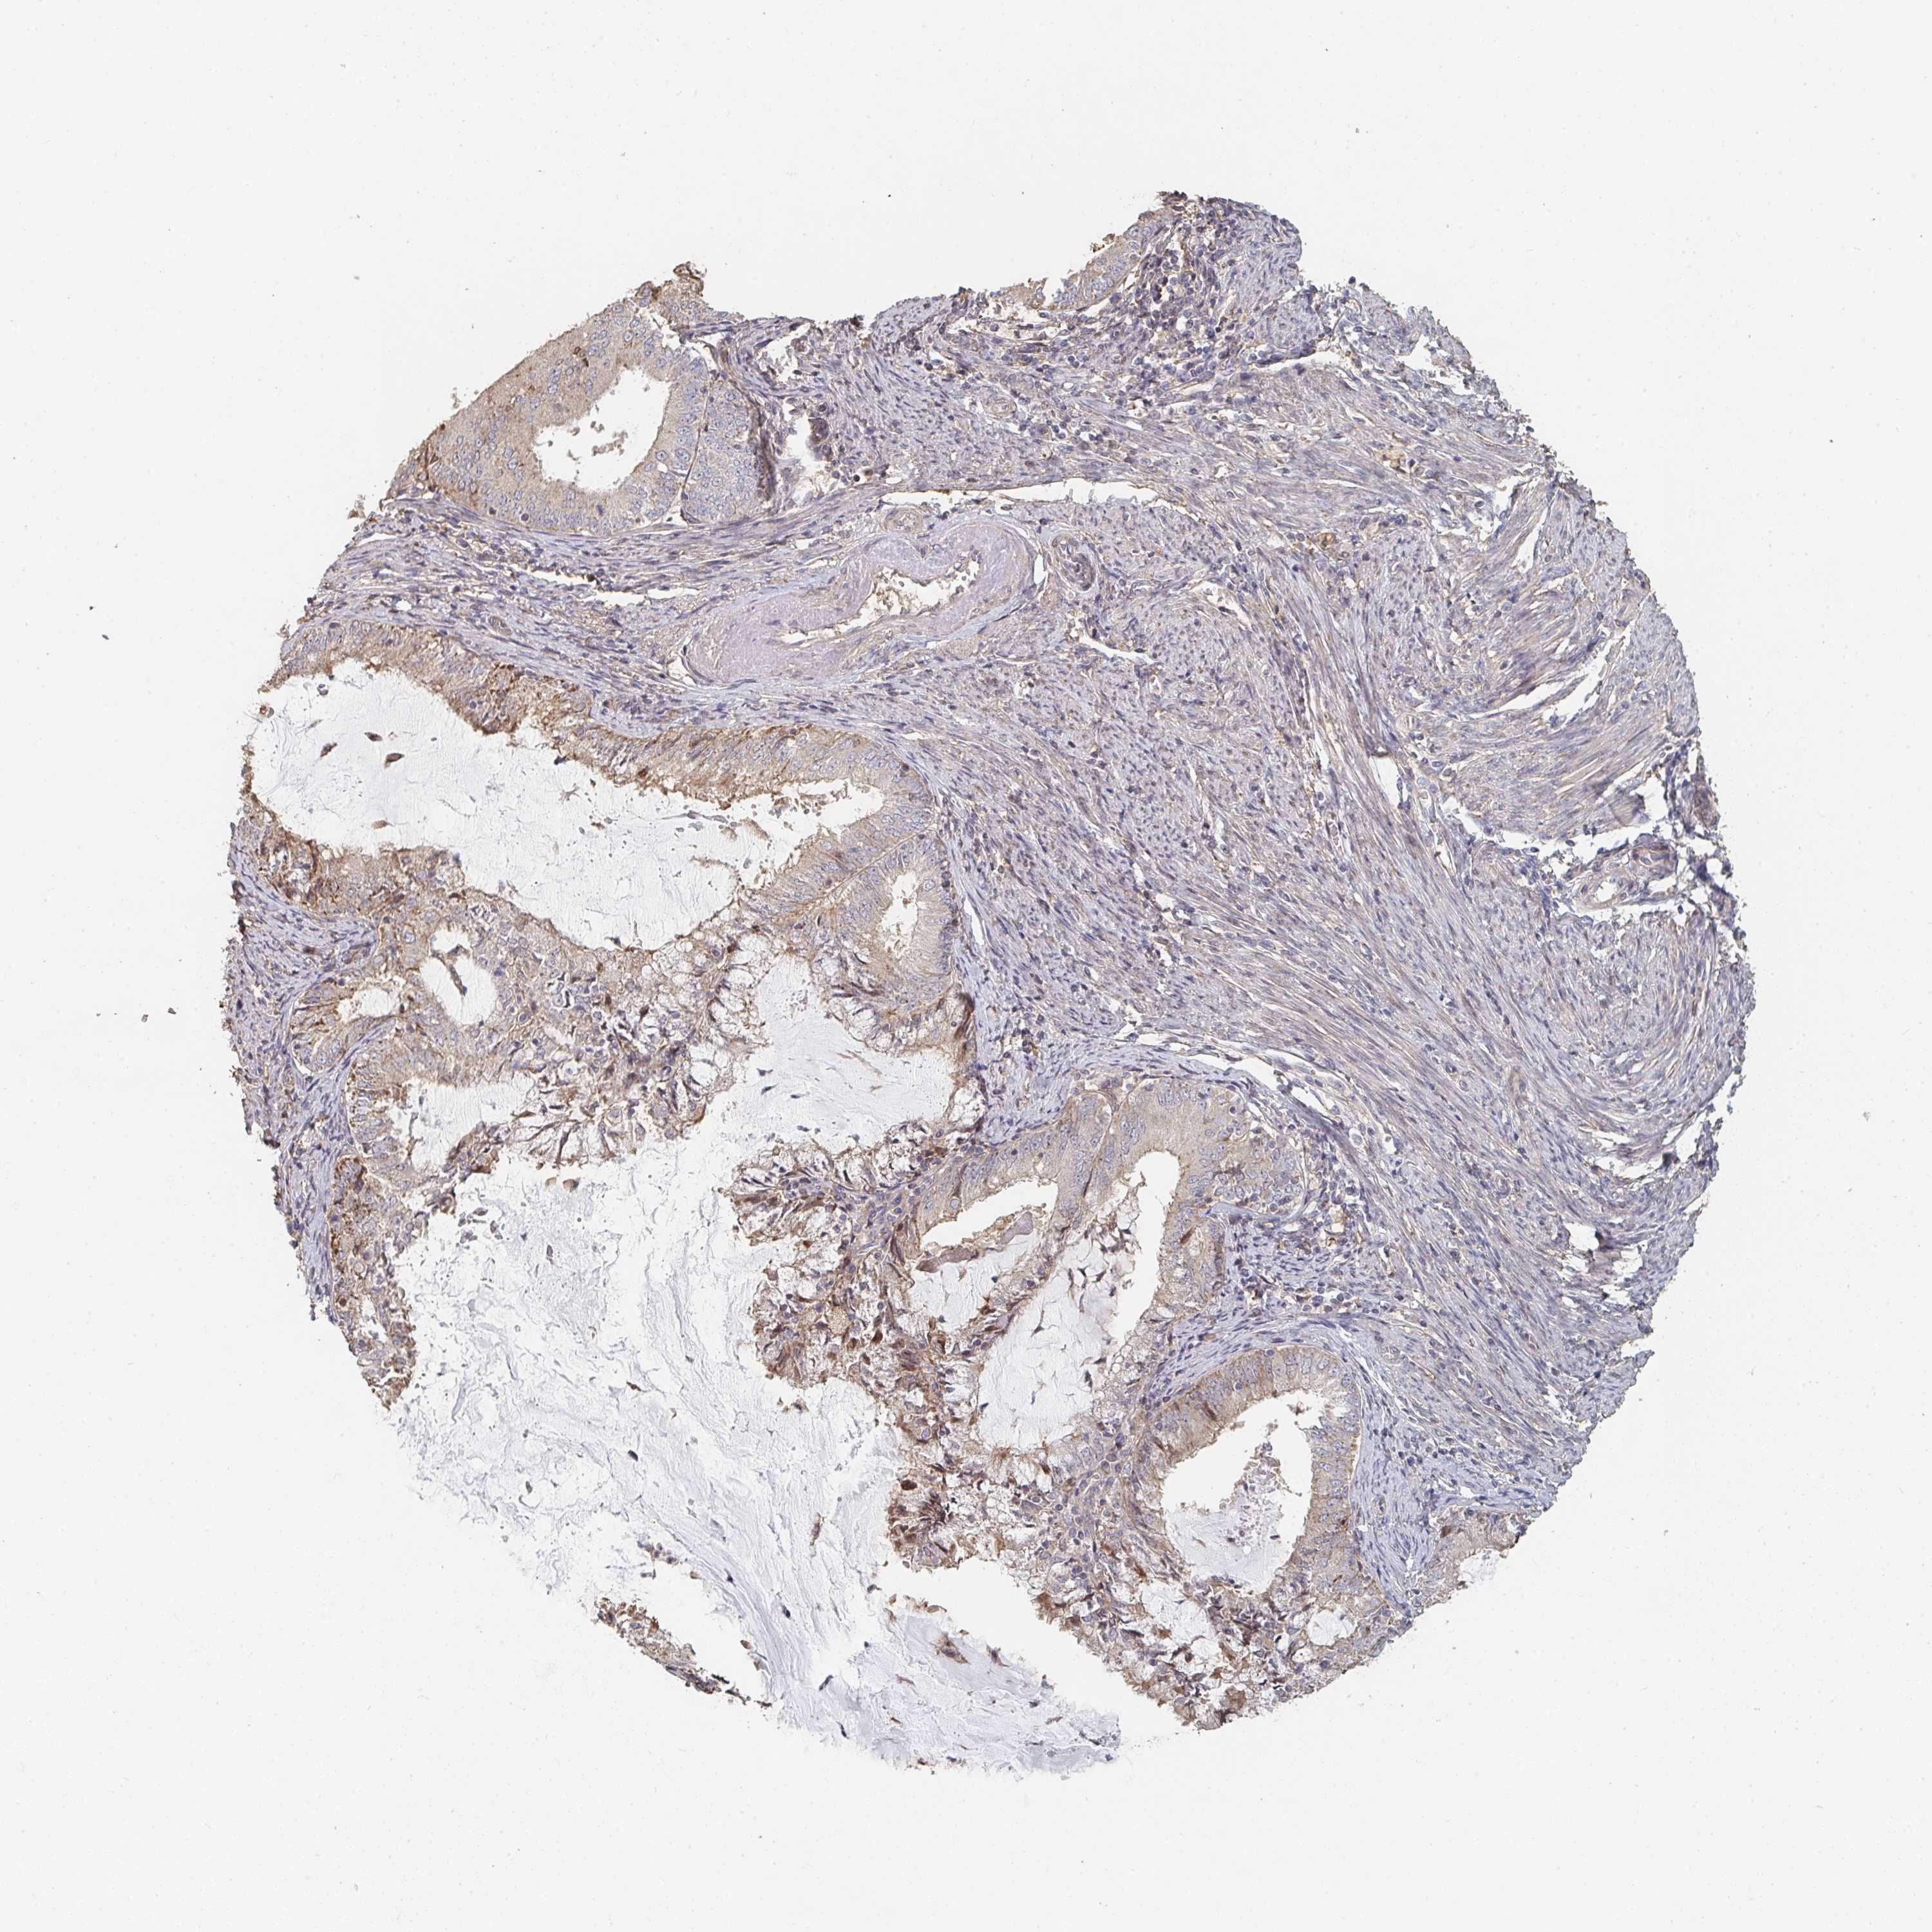

ENDOMETRIAL CANCER - Protein expressioni

A mouse-over function shows sample information and annotation data. Click on an image to view it in a full screen mode. Samples can be filtered based on level of antibody staining by selecting one or several of the following categories: high, medium, low and not detected. The assay and annotation is described here.

Note that samples used for immunohistochemistry by the Human Protein Atlas do not correspond to samples in the TCGA dataset.

Antibody stainingi

Antibody staining in the annotated cell types in the current human tissue is reported as not detected, low, medium, or high, based on conventional immunohistochemistry profiling in selected tissues. This score is based on the combination of the staining intensity and fraction of stained cells.

Each image is clickable and will lead to virtual microscopy that enables deeper exploration of all samples and also displays staining intensity scores, fraction scores and subcellular localization as well as patient and tissue information for each sample.

Antibody HPA031335

Antibody CAB004076

Antibody CAB080153

Antibody CAB080157

Staining

High

Medium

Low

Not detected

Intensity

Strong

Moderate

Weak

Negative

Quantity

>75%

75%-25%

<25%

None

Location

Nuclear

Cytoplasmic/membranous

Cytoplasmic/membranous,nuclear

Adenocarcinoma, NOS

Neoplasm, malignant, NOS

Carcinoma, NOS

Adenocarcinoma, metastatic, NOS